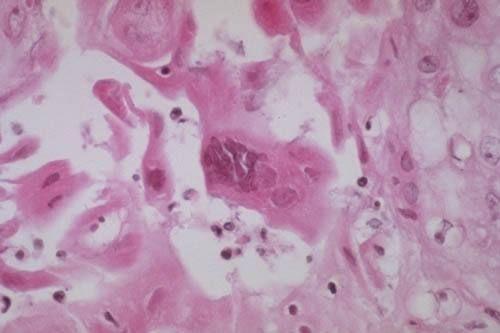

相关图片